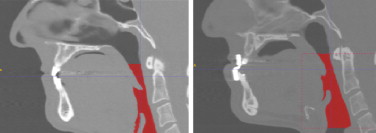

De acuerdo con la metodología de análisis adoptada se consideran 2 situaciones del paciente, una inicial sin aparato bucal y otra funcional con el dispositivo mandibular en una de las posiciones prefijadas para el diagnóstico (fig. 9 ). Para identificar e interpretar correctamente tanto la geometría como los resultados obtenidos en el cálculo fluido-dinámico realizado se subdivide el dominio de análisis mediante 17 cortes transversales (incluyendo las secciones de entrada y salida) (fig. 10 ).

Imagen médica sagital a) sin aparato bucal, b) con aparato bucal.

Figura 9.